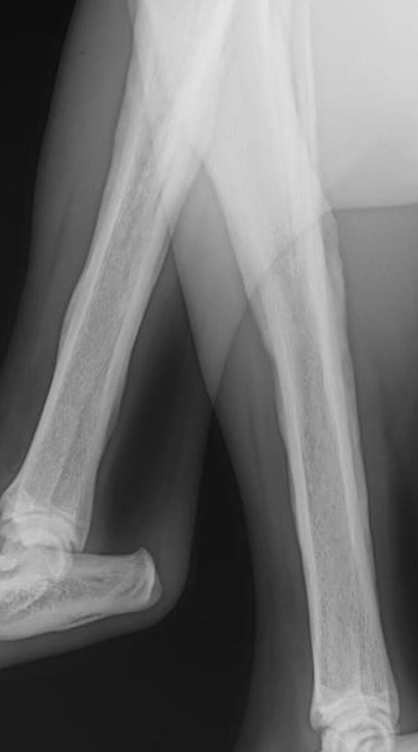

what is hypertrophic osteopathy (HO)?

periosteal proliferation of new bone along shafts of long bones associated with malignant and non-malignant diseases

how/where does hypertrophic osteopathy appear on rads?

symmetrical periosteal new bone formation, nodular or speculated

classically radiating 90degrees from long axis